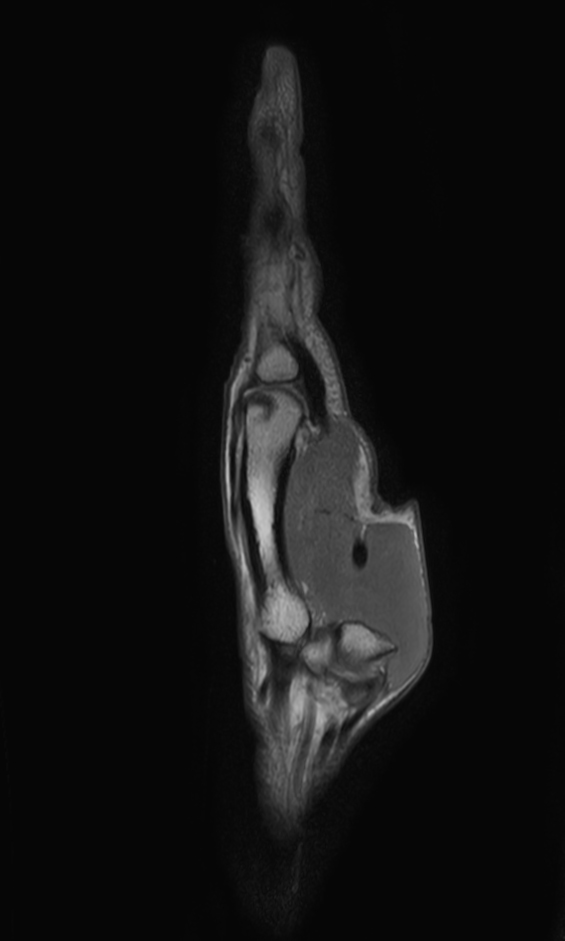

Sagittal PDw TSE mDIXON XD (In Phase)

-

Sagittal PDw TSE mDIXON XD (Water only)